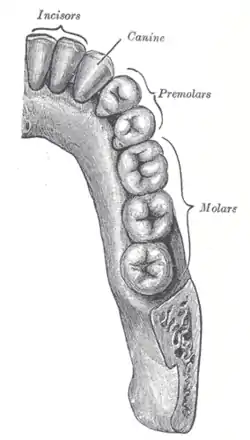

Permanent teeth of right half of lower dental arch, seen from above | |